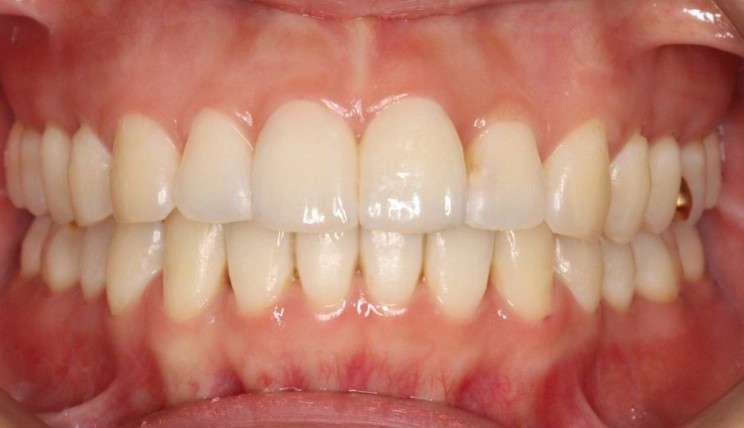

Class II

Class II — or "overbite" — is the condition in which the mesiobuccal cusp of the upper first molar is positioned mesially to the mesiobuccal groove of the lower first molar instead of both being aligned, affecting the occlusal relationship between both dental arches.

Patient Information:

Age: 24

Gender: Female

Invisalign Treatment Option: Invisalign Comprehensive

Total Treatment Time:

21 Months